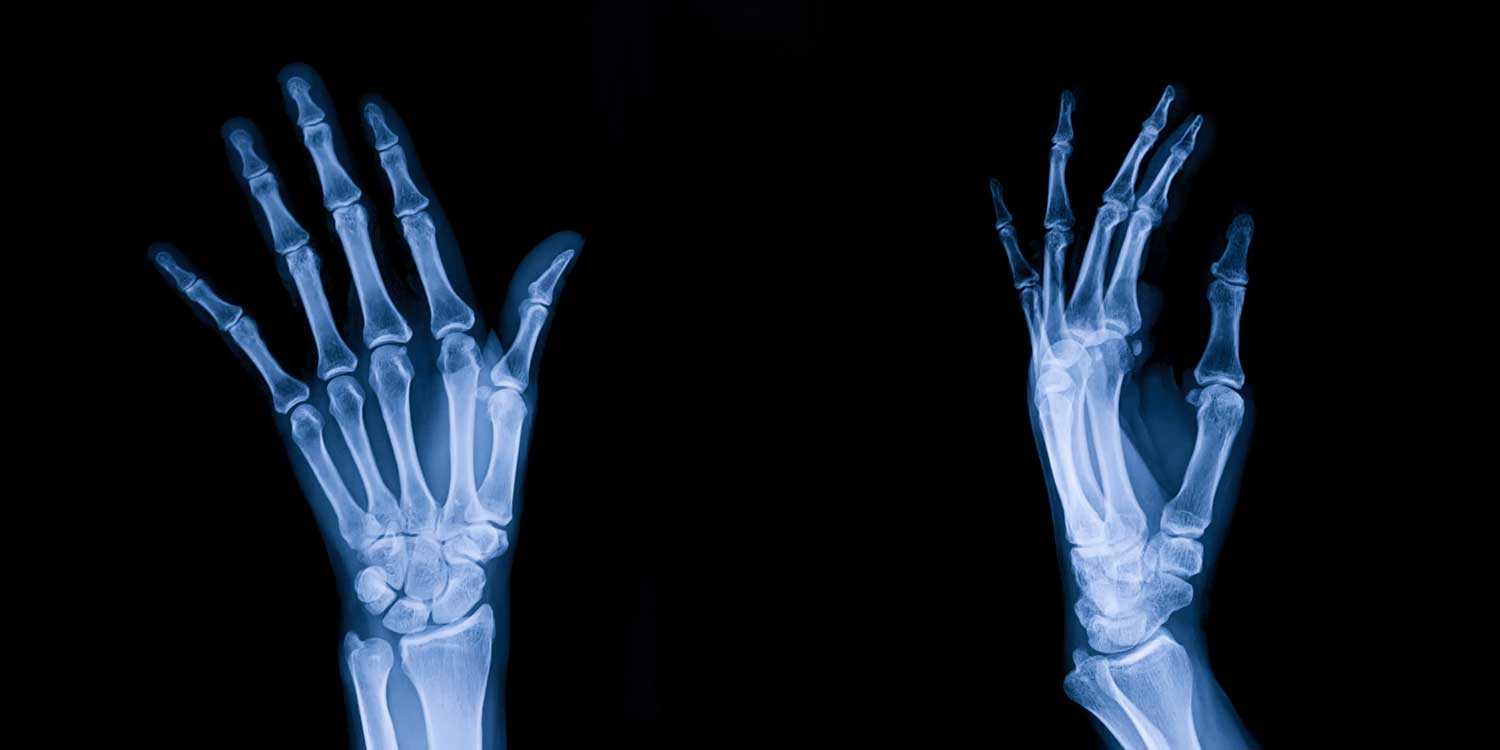

A hand X-ray is one of the most diagnostically informative imaging studies in medicine. In a single painless exam lasting about 10 minutes, it can reveal fractures, dislocations, arthritis, joint damage, bone tumors, foreign bodies, and deformities — providing your doctor with the detailed information needed to guide treatment.

A hand X-ray produces detailed images of all the bones and joints of the hand and wrist, including the phalanges (the 14 finger bones), the metacarpals (the 5 palm bones), and the carpals (the 8 small wrist bones), as well as every joint connecting them. Dense bone appears white; soft tissues and cartilage appear in shades of gray; air and foreign bodies produce their own distinct patterns.

A standard hand X-ray study consists of three views taken from different angles. Each provides distinct and complementary information.

The PA (posteroanterior) view is the frontal view taken with the hand flat, palm down on the detector. It is the primary view for assessing joint spaces, evaluating arthritis distribution, measuring bone alignment, and identifying most fractures.

The oblique view rotates the hand approximately 45 degrees. It separates the overlapping metacarpal shafts and allows clearer visualization of the metacarpal heads, the PIP joints, and the radial or ulnar aspects of the bones — revealing fractures and erosions that can be hidden in the PA view by overlapping bone.

The lateral view is taken with the hand on its side. It is essential for assessing anterior or posterior displacement of fracture fragments, evaluating joint alignment and dislocations, and viewing the carpal bones in profile.